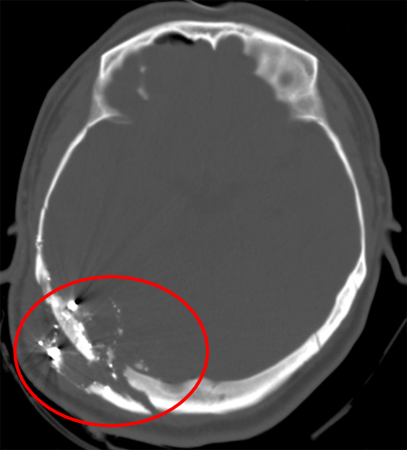

[Figure caption and citation for the preceding image starts]: Gunshot wound with comminuted elevated fracture and pneumocephalus [Citation ends].